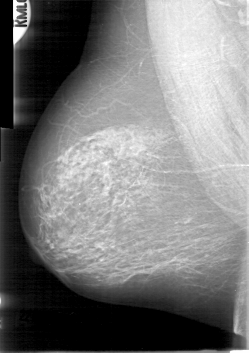

D_4014_1.RIGHT_CC

RIGHT_CC LINES 5341 PIXELS_PER_LINE 3376 BITS_PER_PIXEL 12 RESOLUTION 43.5 NON_OVERLAY